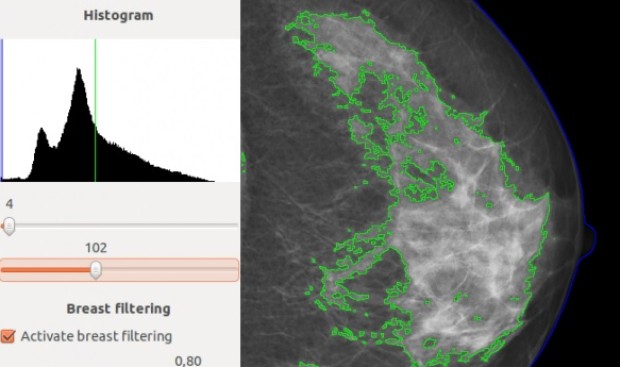

La aplicación informática es fruto del trabajo coordinado de investigadores de Fisabio, la Universitat Politècnica de València y el Instituto de Salud Carlos III (ISCIII). En su versión 4.0, DM-Scan ofrece nuevas prestaciones, como el procesado de mamografías de alta resolución. Utiliza también metodologías de Visión Artificial, Reconocimiento de Formas y Aprendizaje Automático.

La herramienta cuantifica la proporción de tejido fibroglandular en relación con el tamaño de la mama, diferenciando el tejido denso del graso (la mama está compuesta básicamente de tejido adiposo y tejido fibroglandular). Ofrece así una medida continua y más objetiva que la que los facultativos pueden tener a partir de la inspección visual. De ahí que DM-Scan sea una herramienta óptima para la estimación del riesgo de padecer cáncer de mama.